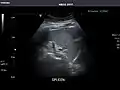

Spleen: Normal in size.

Spleen -